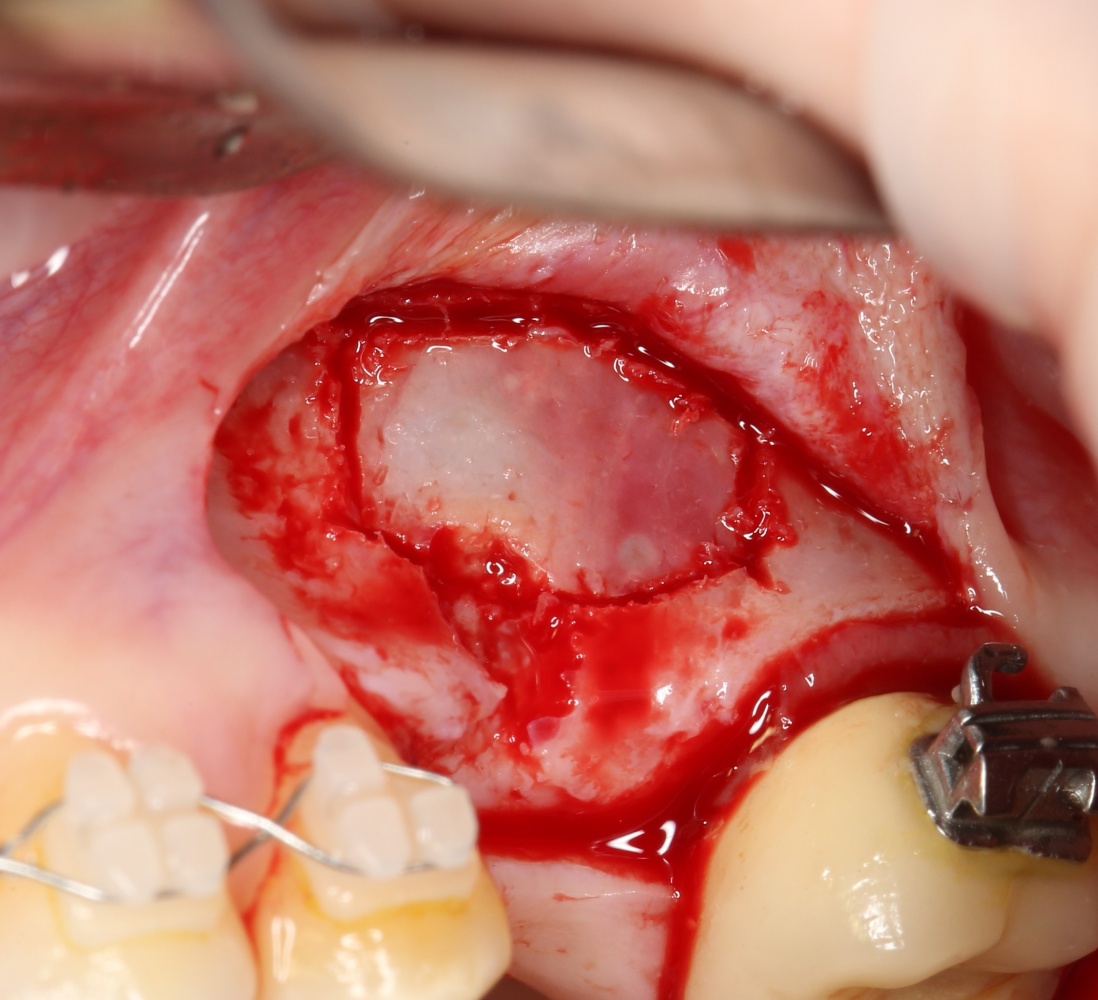

Вариант #3. Использование барьерных мембран

По сути, это «классический» вариант закрытия перфораций шнайдеровой мембраны. Суть проста — мы используем барьерную мембрану типа Bio-Gide или Jason, перекрывая дефект, в среднем, на 30%. Таким образом, мы можем перекрыть даже очень большую перфорацию с достаточно предсказуемым результатом:

Сначала обнаруживаем и выделяем дефект слизистой так, чтобы он максимально уменьшился:

подбираем барьерную мембрану, подгоняем ее по размеру:

приклеиваем получившуюся «заплатку» и заполняем субантральное пространство графтом: